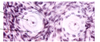

developing antral follicle

antral follicle

graffian follicle ready to ovulate